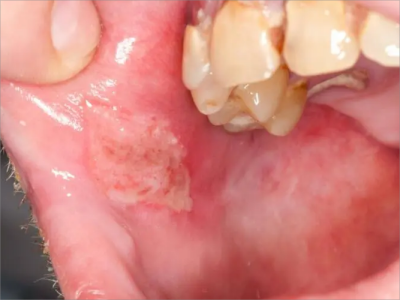

口腔尖锐湿疣症状图片

口腔尖锐湿疣好发于舌、牙龈、腭等部位,表现为单个或多个无痛性的疣状结节,有蒂或无蒂,可逐渐增大或融合,形成菜花状、乳头状赘生物,颜色呈肉色或苍白色,患者可有异物感。